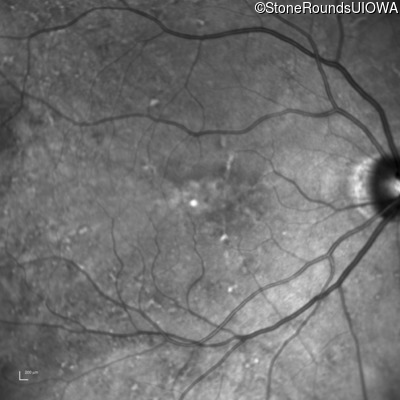

Infrared Fundus Photograph - Left - 20/40 +1

Exemplar